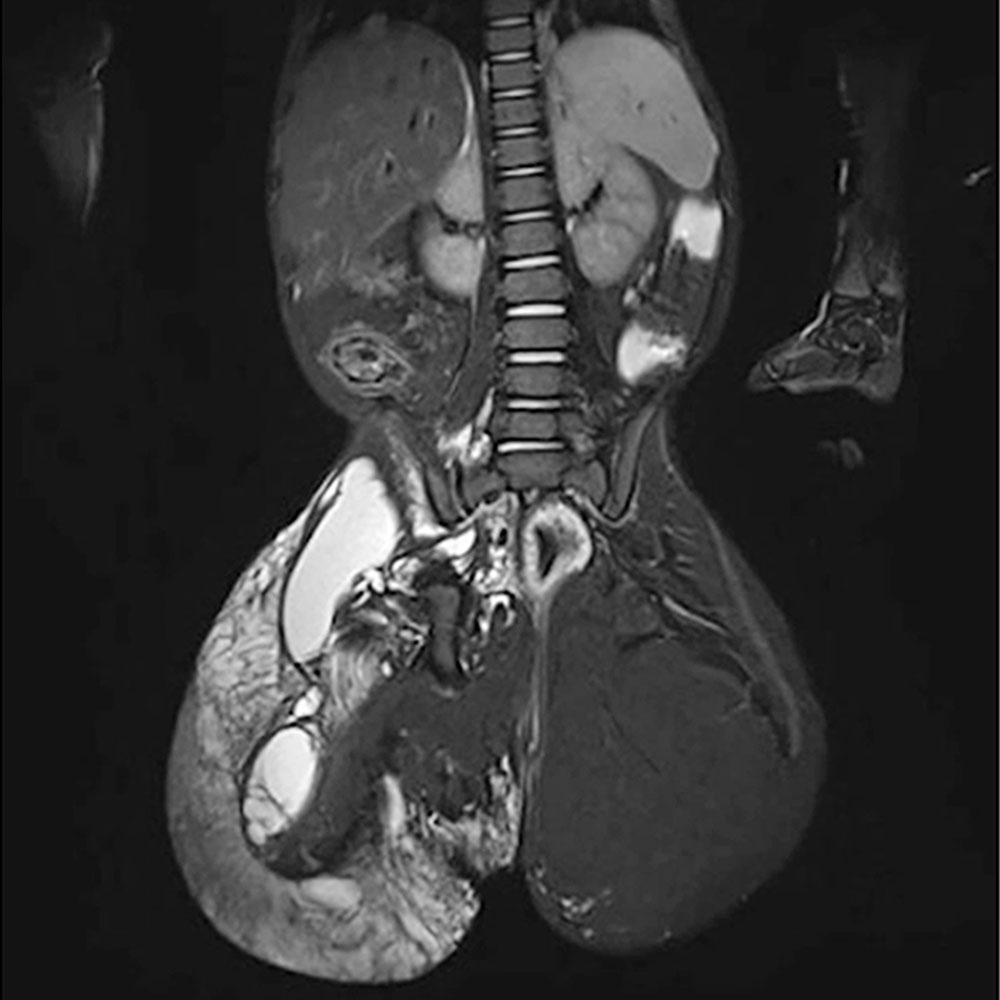

On the other hand, hemihyperplasia or circumscribed overgrowth syndromes and asymmetric hyperplasia syndromes are often associated with scoliosis that may be due to asymmetric growth of the vertebral bodies, analogous to the development of leg length discrepancy. These are to be regarded as syndromic forms of scoliosis.

In CLOVES syndrome, scoliosis is considered a typical concomitant symptom and represents the “S” in the name of this disorder.

In patients with vascular anomalies, diagnosis of scoliosis should usually be further evaluated by MR imaging of the spine to distinguish whether the spinal curvature is due to a vascular malformation in the spine itself (e.g., in CLOVES syndrome) or a possible leg length discrepancy. On the other hand, it may be an idiopathic scoliosis that is present in the patient independently of the vascular malformation.

In addition, the vertebral bodies themselves or their immediate surroundings are sometimes involved in the vascular malformation in terms of pathological vessels. This complicates surgical treatment of scoliosis considerably and requires prior interventional repair of these vessels (e.g., by sclerotherapy or embolization).